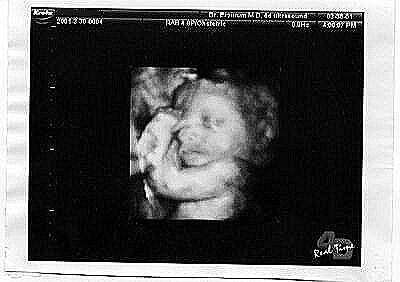

انظري اليه في الاسبوع ال38

وهذه صور أجنة توأم عبر جهاز موجات فوق الصوتية :